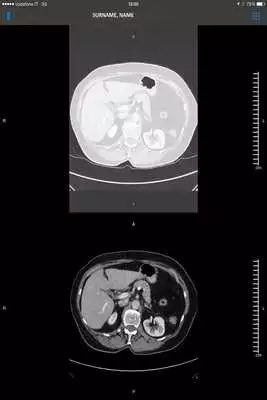

SUITESTENSA Mobile supports software-based medical image viewing for review of radiological images on the Android devices. It includes 2-D viewing, Maximum Intensity Projection (MIP including slabbing up to 50 mm), Multi Planar Reformatting (MPR) for axial, sagittal and coronal views, and 3-D volume rendering. All functions are accessed through the touch screen interface on the mobile client software.SUITESTENSA Mobile is not to be used for mammography.